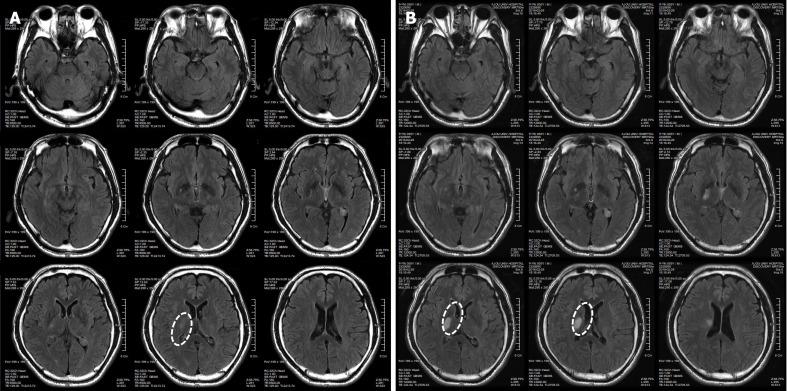

患者于2018年2月17日至18日出現(xiàn)暫時性無力癥狀,早上醒來后突發(fā)急性中風(fēng),導(dǎo)致左上肢和下肢癱瘓。患者在大學(xué)醫(yī)院急診室被診斷為Rt紋狀體囊性梗死(圖1A)。他于2018年3月2日出院,僅接受了阿司匹林處方,因為根據(jù)腦計算機斷層掃描 (CT) 掃描,他的腦血管正常,盡管他的病情在住院期間惡化(圖1)。出院當天,他被送往康復(fù)專科醫(yī)院接受長期康復(fù)治療。然后他于2018年3月13日來韓國首爾生物美容與健康公司 (bBHC)-干細胞治療與研究所 (STRI)接受干細胞治療。